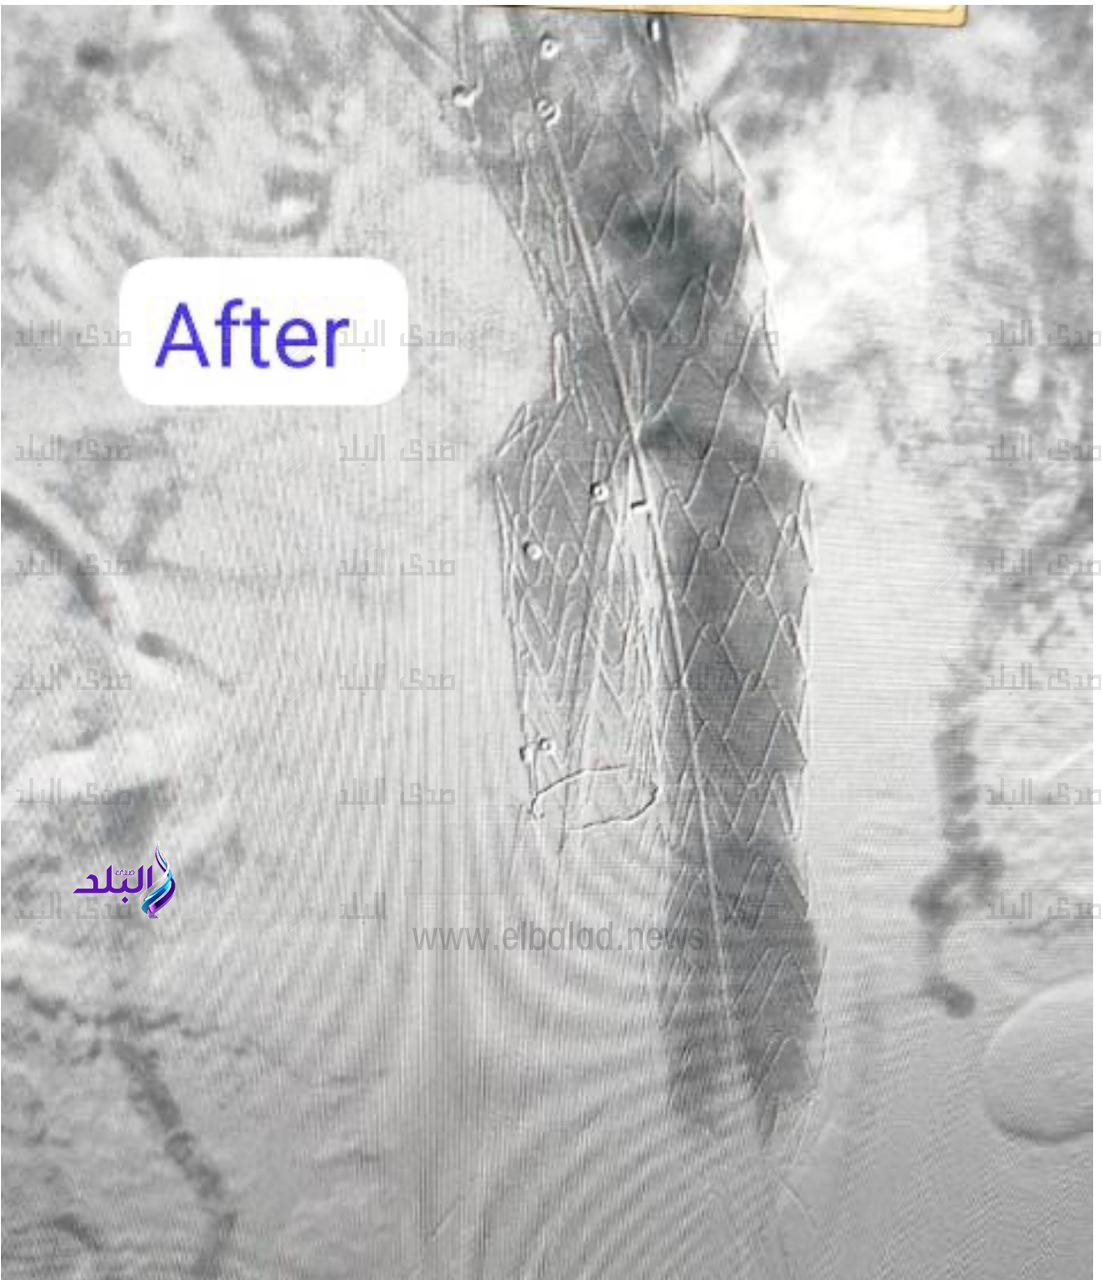

نجح فريق بقسم جراحة الأوعية الدموية بمستشفى بدر التابع لكلية الطب بجامعة حلوان في إجراء تركيب قسطرة دقيقة جداً لمريض يعاني من تمدد كبير في الشريان الأورطي والشريان الحرقفي الايمن، حيث تم تثبيت دعامات مغطاة على هذين الشريانين لمنع انفجارهما، مما ساهم في إنقاذ حياته.

تركيب قسطرة دقيقة جداً لمريض يعاني من تمدد كبير في الشريان الأورطي والشريان الحرقفي الايمن